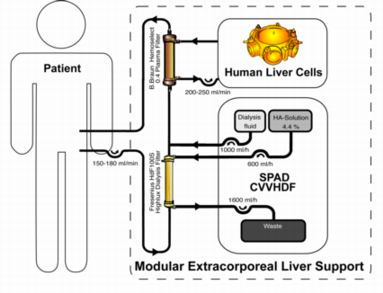

The patients are treated with the modular extracorporeal liver support concept. A bioreactor is charged with human liver cells, obtained from discarded cadaveric grafts, and integrated into an extracorporeal circuit with continuous single pass albumin dialysis and continuous veno-venuous hemodiafiltration for detoxification and fluid reduction.

Venous access is gained by placing a double-lumen dialysis catheter into either the internal jugular or the femoral vein. Blood is pumped through a hollow fiber plasma filter (Plasmaselect 0.4, Braun) at a rate of 150-250 mL/min. If necessary, a continuous infusion of heparin has to be performed for anticoagulation in order to achieve an activated clotting time of 160-180 seconds (ACT, Fresenius, Oberursel, Germany). For continuous exchange with the CellModule the bioreactor is connected to the plasma circuit in counter-directional flow mode at 150-200 mL/min. The total extracorporeal volume is approximately 110 ml in the blood circuit, and 900 ml of plasma in the bioreactor and associated circuitry.

The DetoxModule enables albumin-dialysis via a standard high-flux dialysis cartridge. The patient’s blood flows through a circuit with a high-flux hollow fiber hemodiafilter (Fresenius HdF 100S polysulfone high-flux haemodiafilter, Fresenius AG, Bad Homburg). The other side of this membrane is cleansed by an albumin solution in counter-directional flow and discarded after passing the filter. One liter of a 4.5-liter bag with standard bicarbonate buffered dialysis solution is replaced by 1000 ml of 20% human albumin solution, resulting in 4.4% albumin solution. During therapy, the blood pump speed is adjusted to 130 –180 ml/min; the dialysis-pump speed is 600 ml/h.

12 Patients with acute liver failure (n=3), primary non-function after LTx (PNF, n=3) and acute-on-chronic liver failure (AoCLF, n=6) were treated.

Venous access is gained by placing a double-lumen dialysis catheter into either the internal jugular or the femoral vein. Blood is pumped through a hollow fiber plasma filter (Plasmaselect 0.4, Braun) at a rate of 150-250 mL/min. If necessary, a continuous infusion of heparin has to be performed for anticoagulation in order to achieve an activated clotting time of 160-180 seconds (ACT, Fresenius, Oberursel, Germany). For continuous exchange with the CellModule the bioreactor is connected to the plasma circuit in counter-directional flow mode at 150-200 mL/min. The total extracorporeal volume is approximately 110 ml in the blood circuit, and 900 ml of plasma in the bioreactor and associated circuitry.

The DetoxModule enables albumin-dialysis via a standard high-flux dialysis cartridge. The patient’s blood flows through a circuit with a high-flux hollow fiber hemodiafilter (Fresenius HdF 100S polysulfone high-flux haemodiafilter, Fresenius AG, Bad Homburg). The other side of this membrane is cleansed by an albumin solution in counter-directional flow and discarded after passing the filter. One liter of a 4.5-liter bag with standard bicarbonate buffered dialysis solution is replaced by 1000 ml of 20% human albumin solution, resulting in 4.4% albumin solution. During therapy, the blood pump speed is adjusted to 130 –180 ml/min; the dialysis-pump speed is 600 ml/h.

12 Patients with acute liver failure (n=3), primary non-function after LTx (PNF, n=3) and acute-on-chronic liver failure (AoCLF, n=6) were treated.